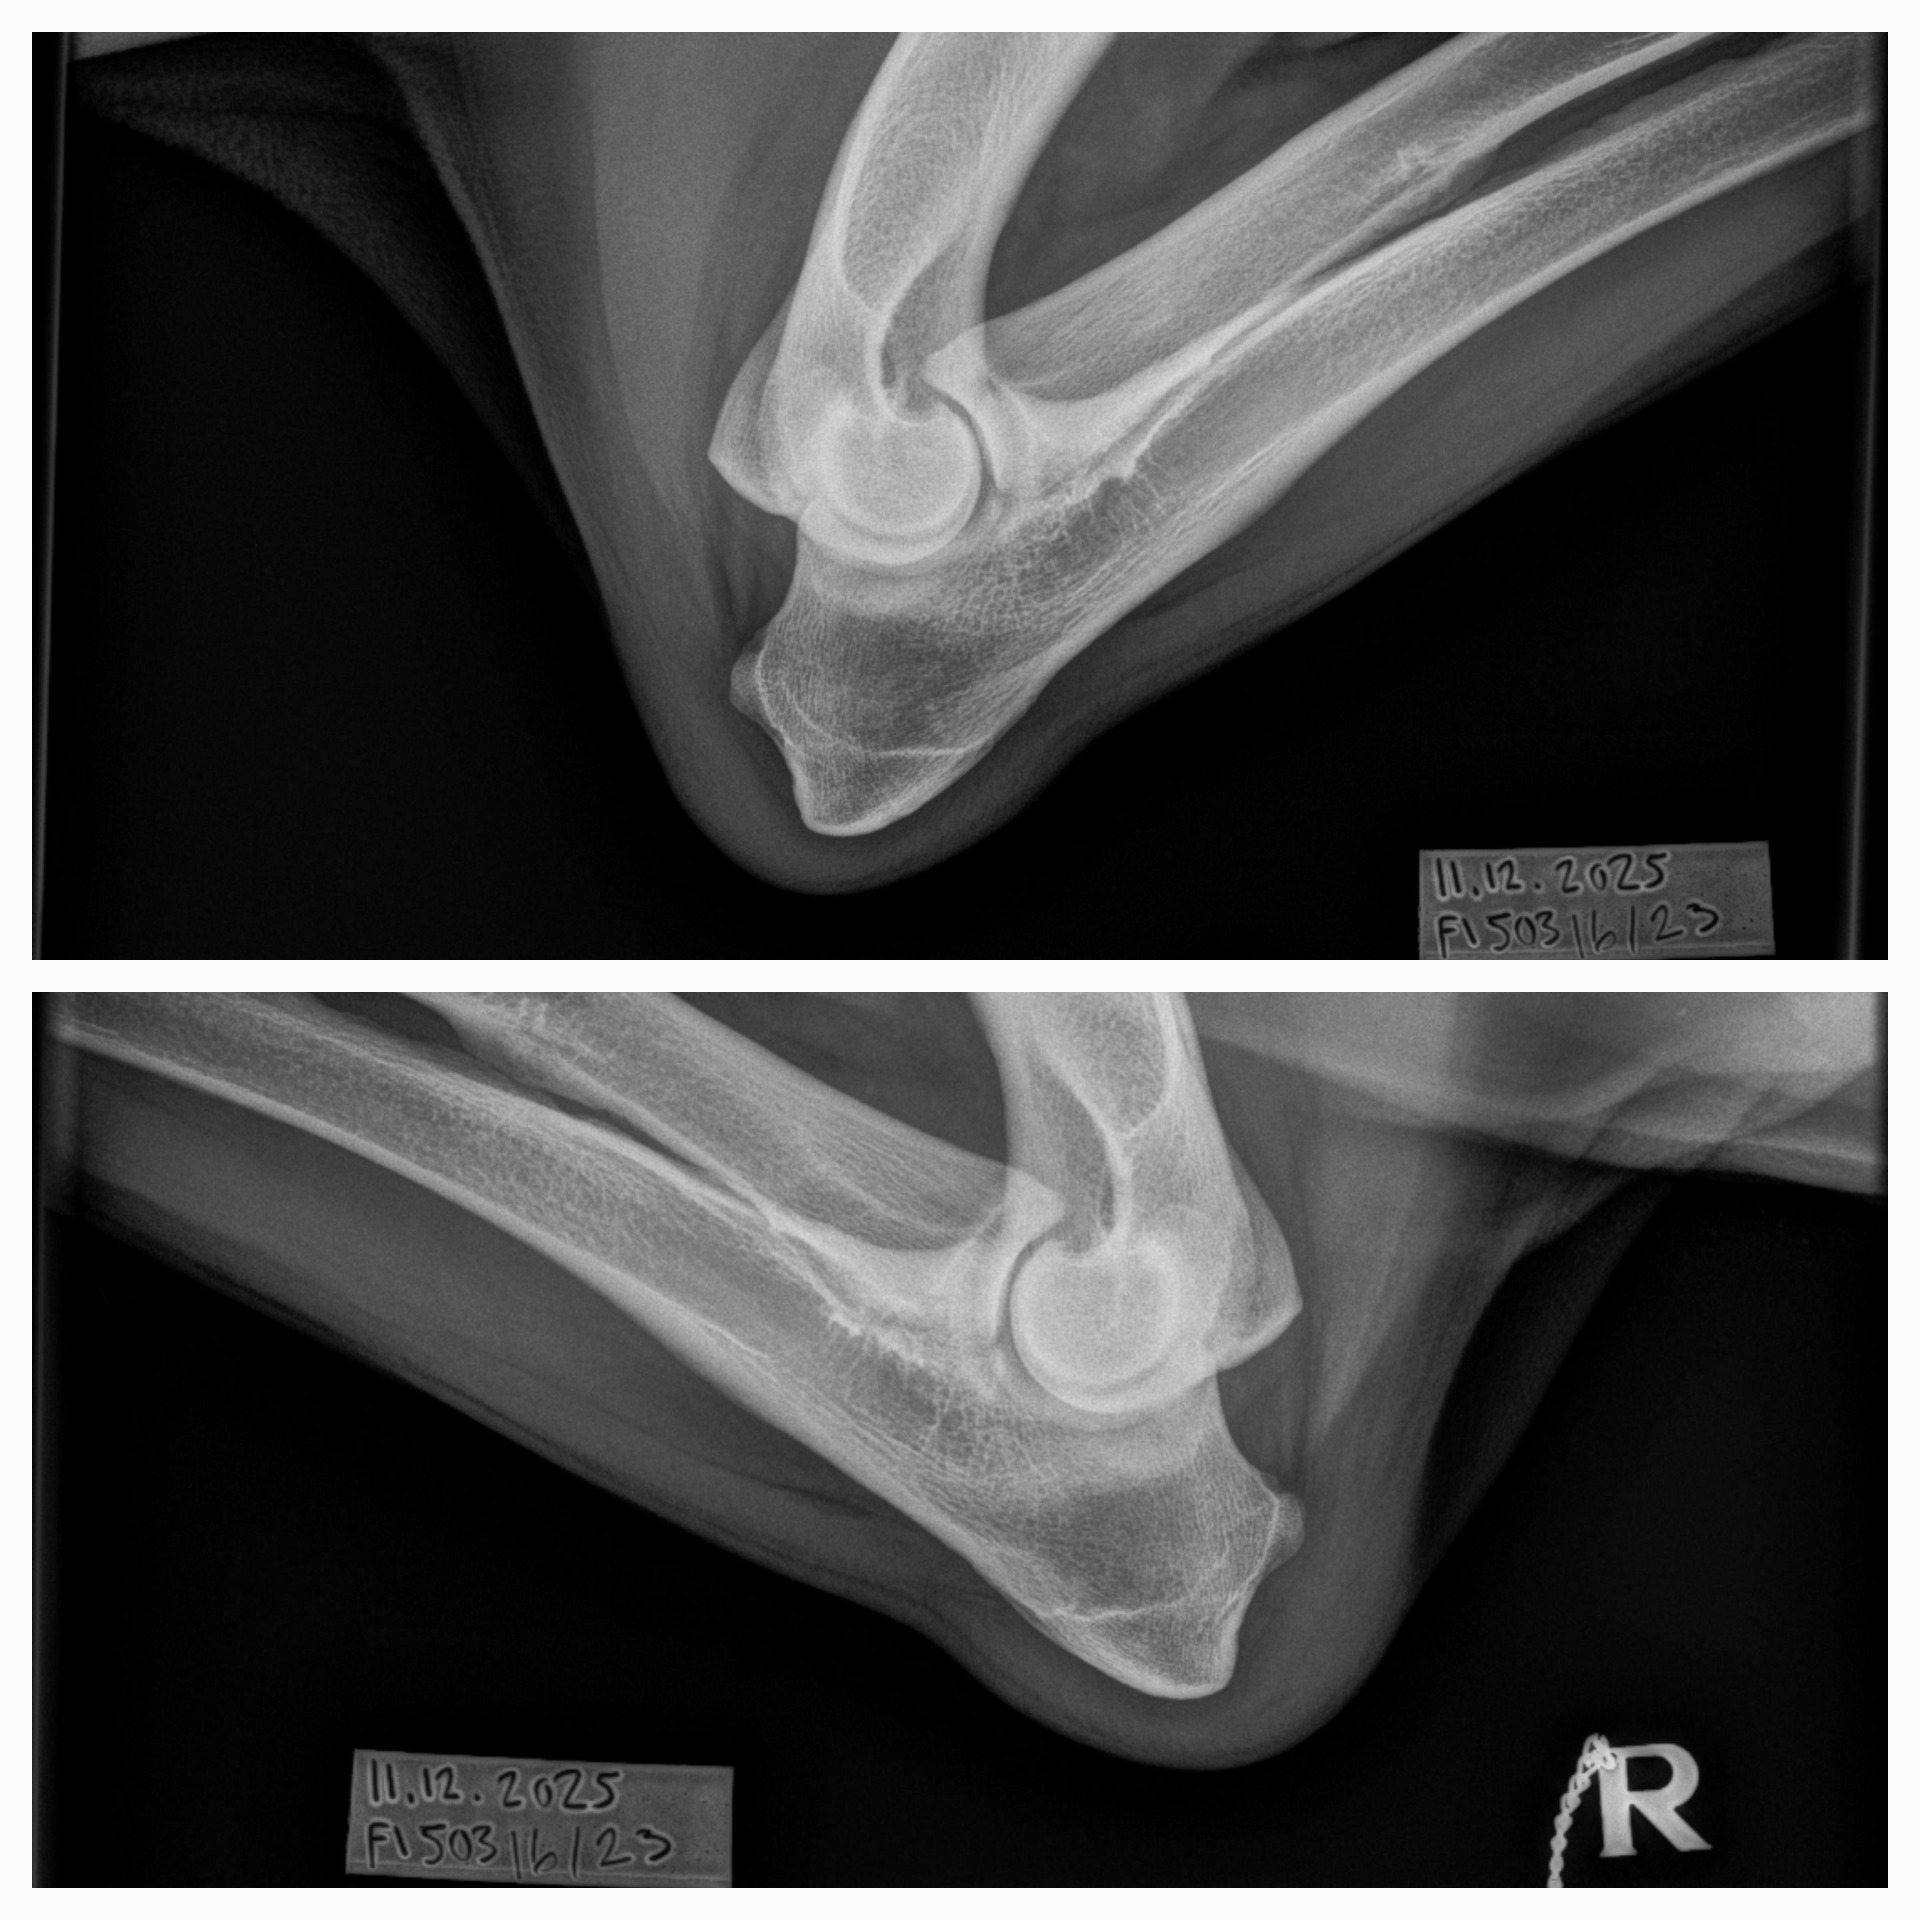

| 12.12.2025 | kyynärniveldysplasia lonkkaniveldysplasia | 0/0 A/A |